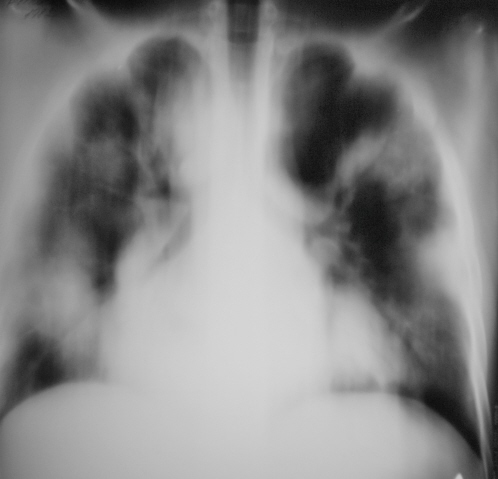

Пациент находится в реанимации, без сознания, информации "нуль".

Кто, что может посоветовать. Позднее будут томограммы, правда довольно низкого качества.

Думаю, что в первую очередь стоит остановиться на двухсторонней пневмонии, особенно если кровь воспалительная, лихорадка и хрипы при аускультации. Плюс праволежащая аорта, если я не ошибаюсь? А на фоне антибактериальной терапии отследить динамику. Если не будет положительного эффекта от лечения - тогда рассмотреть другие варианты (только еще не придумала, какие!).

Валентин Львович! А с какой патологией пациент находится в реанимации, как долго? По рентгенограммам и ТМГ можно сказать о двусторонней пневмонии (гипостатическая?). Возможно развитие альвеолярного отека легких. И третий вариант дистресс-синдром, но под большим вопросом.